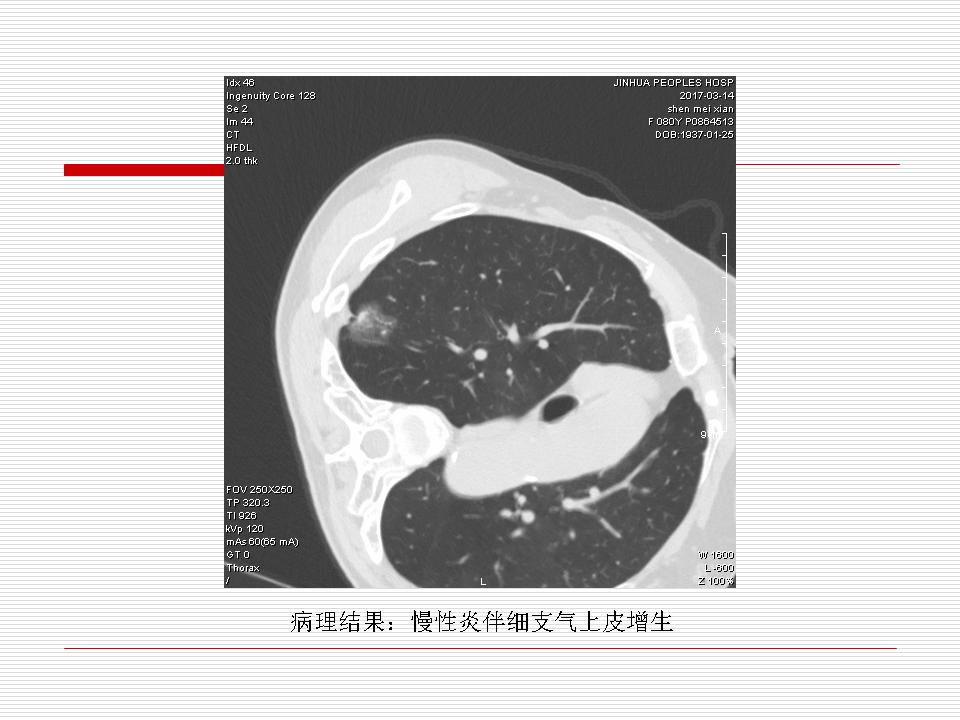

肺部阴影永恒且最重需要鉴别的是:到底是炎症还是肿瘤?但临床的病例中的影像表现难以界定或有些肿瘤特征,同时又有些炎症特点是非常常见的情况。作为临床医生我们怎么去总结分析,并找到之所以是炎症或之所以是肿瘤的细微差别或特点非常重要,也非常有用。2019.12.7浙江省2019年胸心外科学学术年会在宁波召开时,我的临床病例分析与经验总结<那些像肺癌的炎症与像炎症的肺癌>获得在大会交流的机会,以下为该PPT的内容,与你分享,希望对同道有益,有借鉴与启迪。若有探讨与进一不完善的建议,欢迎文末留言讨论: